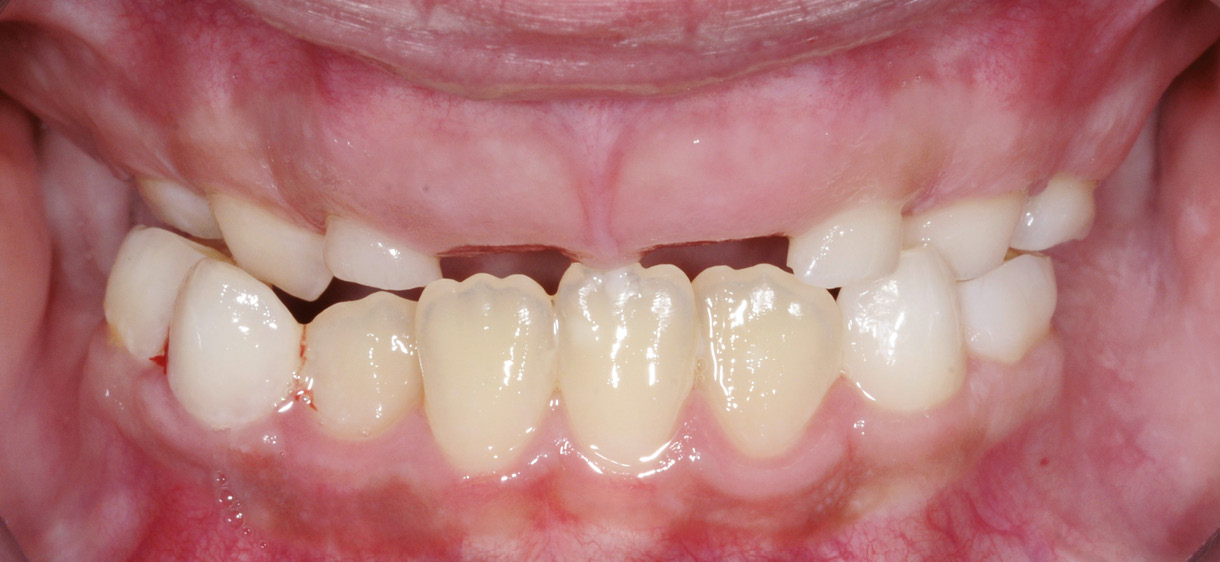

Ce cas est une forme sévère, puisque les quatre quadrants sont touchés ainsi que les dents profondément incluses, correspondant à une forme de DPE bilatérale et bimaxillaire (fig. 1).

Fig. 1 – Vue endobuccale initiale.